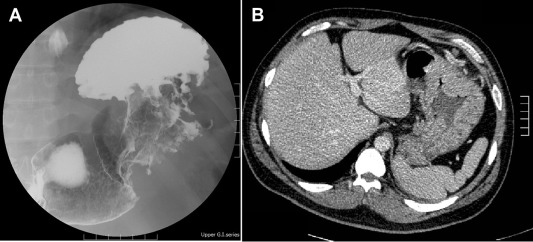

A barium upper gastrointestinal series radiography showed a suspected gastric tumor in the upper body with poor peristalsis and thickened mucosa (Fig. 2 A). An abdominal CT scan also revealed marked folds thickening in the gastric body without any obvious subserosal involvement. The impression from the radiologist was gastric cancer (Fig. 2 B). An EUS demonstrated circumferential thickening (up to 14.1 mm) of the second and third layers of the gastric wall with some anechoic cystic lesions (Fig. 3 ).

(A) Barium fluoroscopic upper gastrointestinal series and (B) upper abdominal ...

Figure 2.

(A) Barium fluoroscopic upper gastrointestinal series and (B) upper abdominal computed tomography. (A) Barium fluoroscopic upper gastrointestinal series reports suspicious gastric tumor of high body with poor peristalsis and thickening mucosa. (B) Abdominal computed tomography reveals marked folds thickening at gastric body without obvious subserosal involvement.